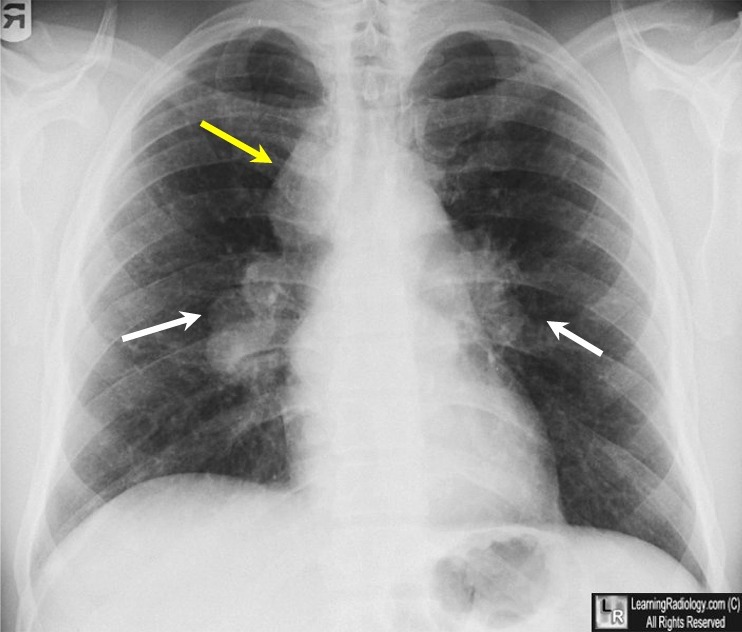

What does bilateral symmetrical hilar enlargement indicate?

Sarcoidosis

What does unilateral hilar enlargement indicate?

Malignancy